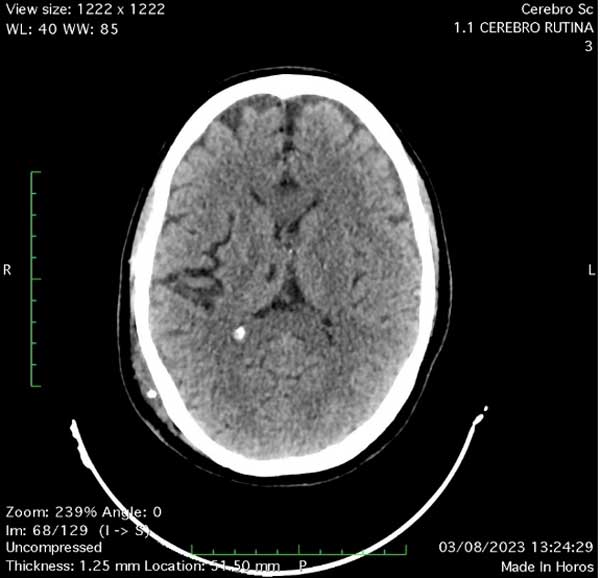

Se decidió realizar una derivación ventriculoperitoneal (VDVP) para remisión total de los síntomas. La paciente estuvo aproximadamente un año libre de enfermedad con control por imágenes satisfactorio (Figura 3). Posteriormente, consultó por reaparición de síntomas. La semiología valvular arrojó pulsor rígido y la TC cerebral de control mostró dilatación ventricular por lo que se efectuó cirugía de revisión en la que se halló disfunción valvular distal secundaria a obstrucción por detritus celulares. Se repermeabilizó el catéter distal y se volvió a colocar en cavidad peritoneal resolviendo la signo-sintomatología que manifestaba. Desafortunadamente presentó una escara cutánea en la herida cefálica con exposición del reservorio valvular que requirió cirugía de toilette y extracción completa del dispositivo más tratamiento antibiótico. Evolucionó con incremento progresivo de los trastornos de la marcha por lo que se programó una tercera ventriculostomía endoscópica (TVE), en la que se observó la impronta del espacio de Virchow-Robin en el tálamo posterior, el piso del tercer ventrículo abierto y la membrana de Liliequist ya fenestrada (Figura 4). Finalmente, se determinó colocar una válvula de derivación ventriculoperitoneal (VDVP) contralateral con evolución favorable.

Figura 3. Imagen de tomografía computada de cerebro en corte axial donde se observa correcta colocación de catéter ventricular y resolución de la hidrocefalia.